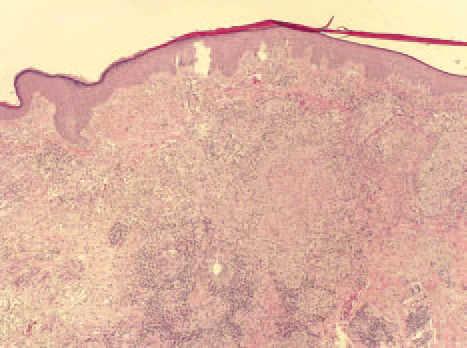

La biopsia de una de las lesiones mostró granulomas epitelioides sin caseificación central en dermis superficial y profunda (fig. 3), así como la existencia de células gigantes multinucleadas (fig. 4).

Figura 3. Hematoxilina-eosina, 4 100.